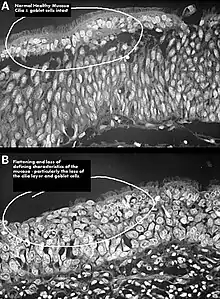

![]() | |

| Altered nasal anatomy after bilateral subtotal inferior turbinectomy, the removal of most turbinate tissue. | |